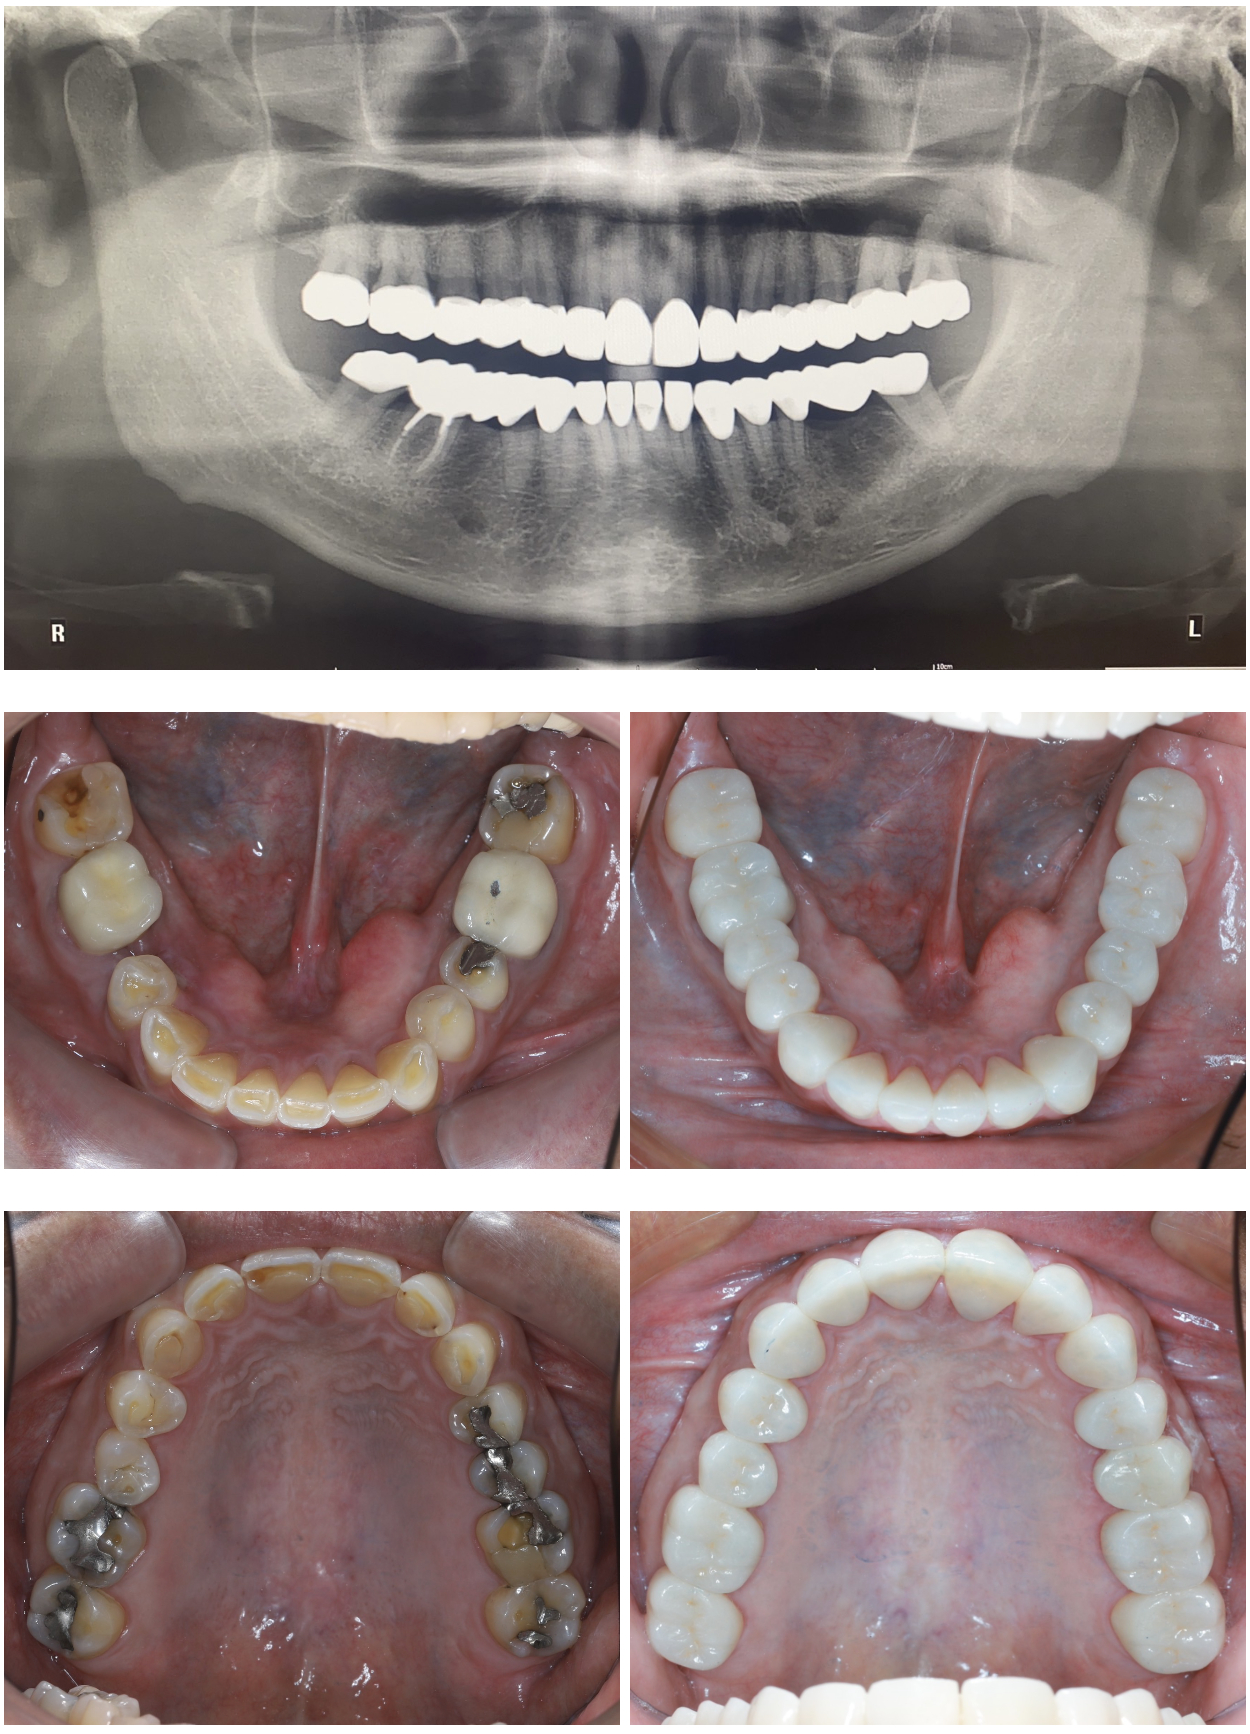

รูปภาพ Belix Dental